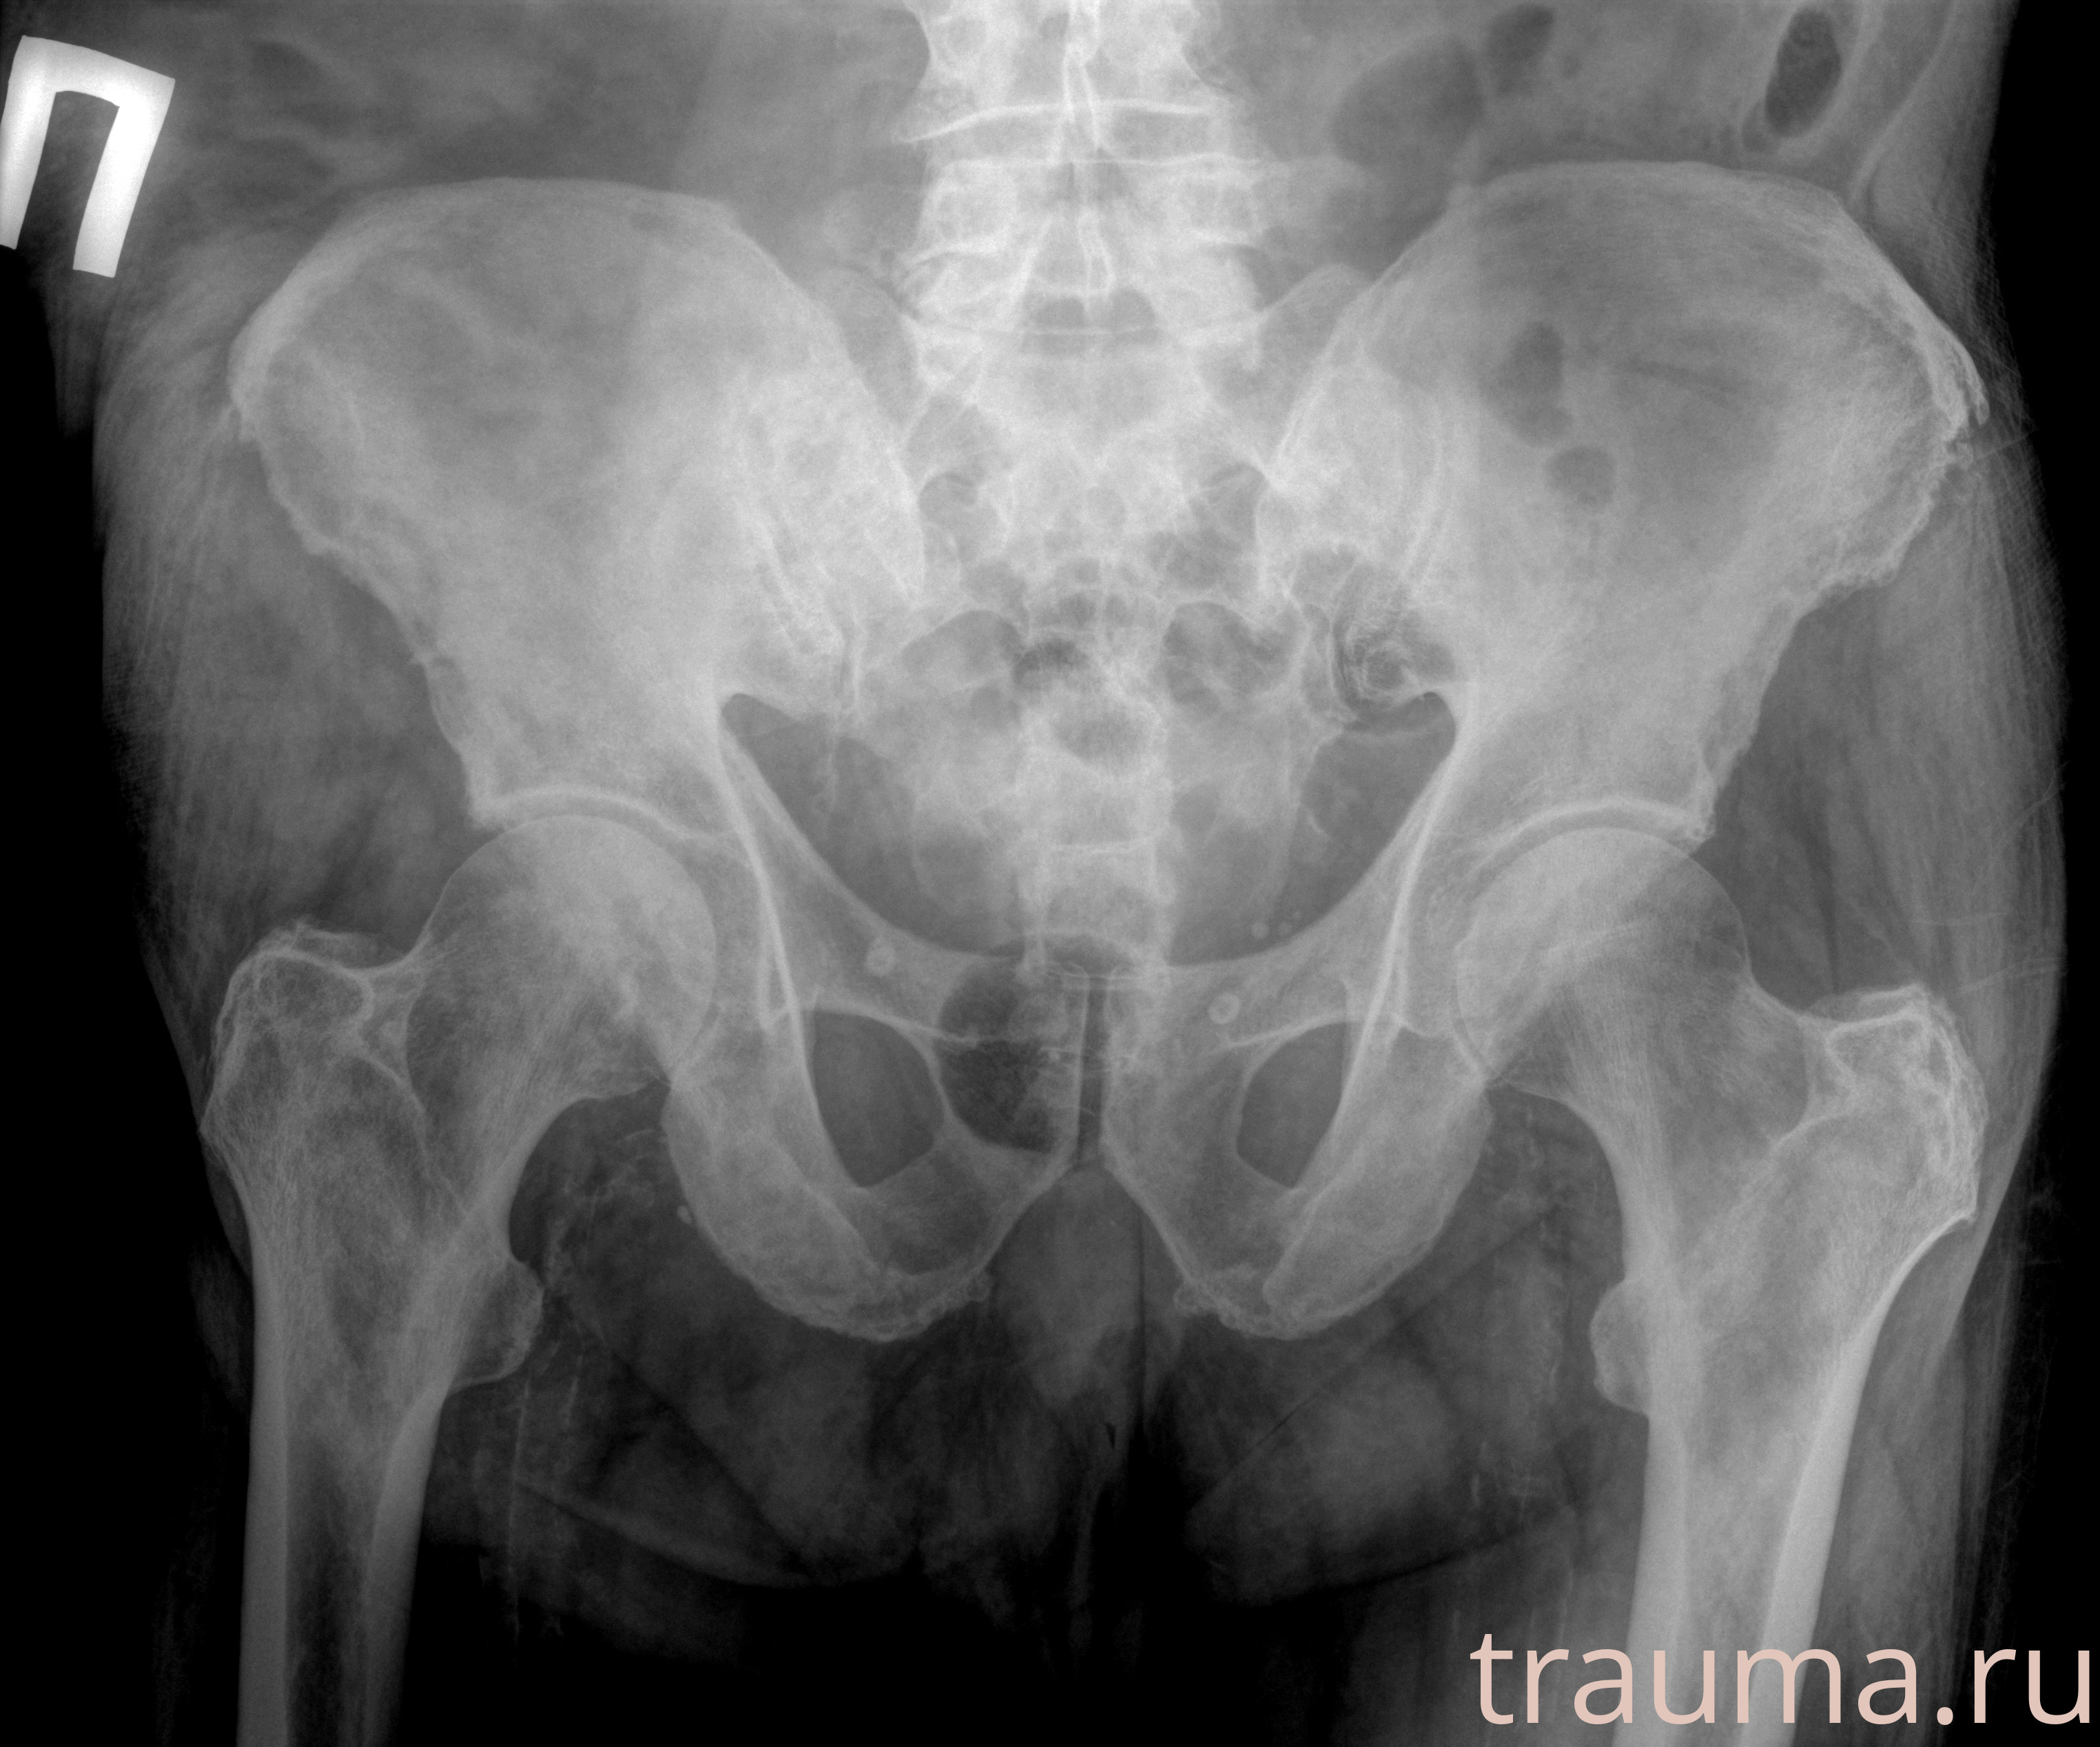

Первая помощь при переломе шейки бедра

Рентген на дому: по вашему адресу приезжает врач-рентгенолог, травматолог-ортопед с мобильным рентгеновским аппаратом, проводит диагностику травмы или заболевания, делает необходимые рентгенограммы, дает рекомендации по дальнейшему лечению. Получить качественные снимки в домашних условиях возможно благодаря уникальной методике, разработанной МосРентген Центром для института  Склифосовского